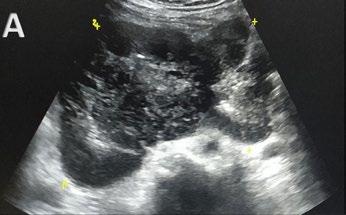

In contrast to acute complications, chronic complications are generally more unique to the Caesarean section itself, and are not typically seen with other surgical procedures, with the exception of incisional hernia. Caesarean scar niche was identified as an important cause of pain and irregular bleeding (Figure 1).

C-section: Caesarean section; US: ultrasound.

A B C D E F G H J K L M I Abstract ● ECR 2024 Creative Commons Attribution-Non Commercial 4.0 ● April 2024 ● Radiology 23

Figure 1: Caesarean scar niche.